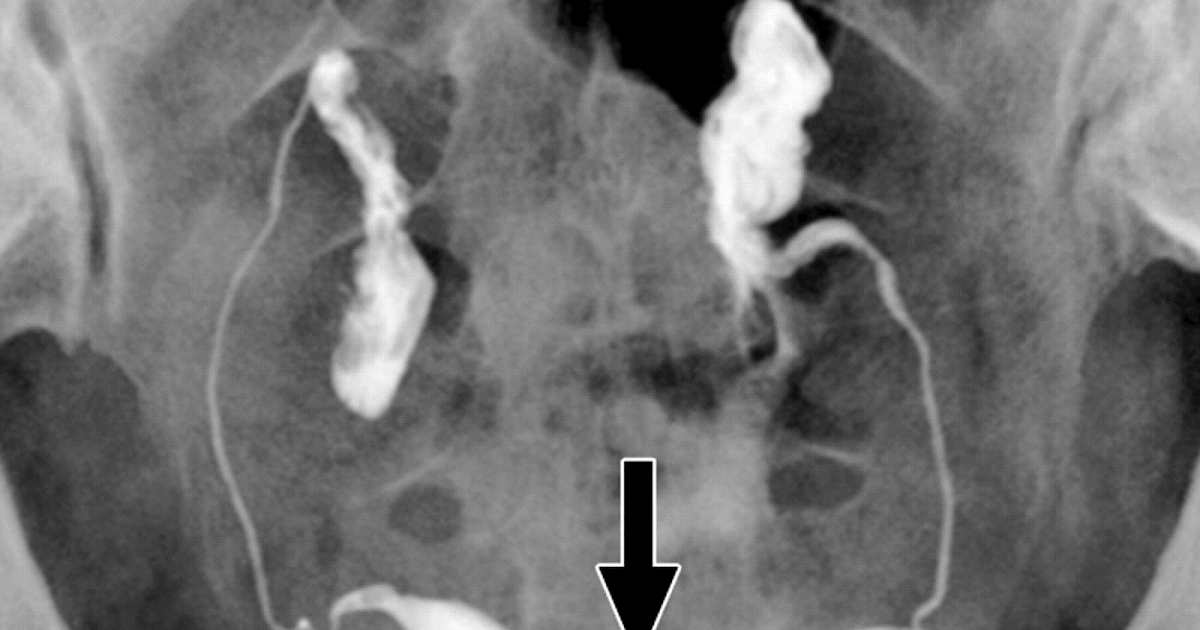

One ended in blighted ovum but my 2 year old and a current pregnancy 24 wks have been successes. I ended up losing the baby in march but my re said that had nothing to do w hsg that it was just chromosomal prob w the egg or cell division. They told me i didnt have any blockages when i went for my results and it is known to clear anyhing or flush things out xxxx. A hysterosalpingogram or hsg is an x ray test where dye is injected through the cervix into the uterus to visualize whether both fallopian tubes are open and if the shape of the uterine cavity is normal.

Hysterosalpingography Imaging Of The Fallopian Tubes And Uterus